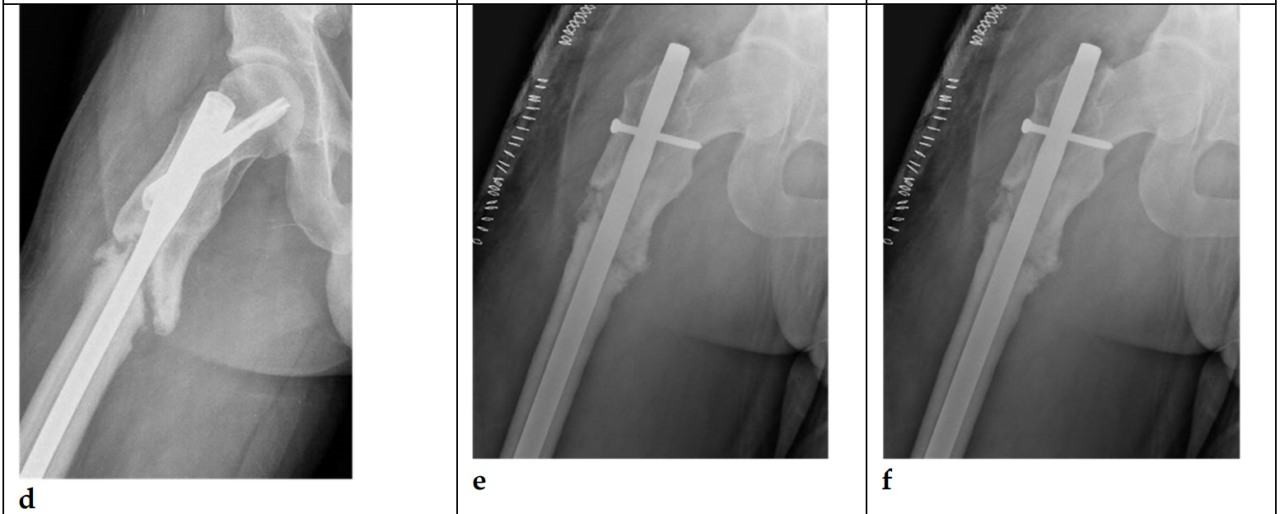

Goodnough等人比较了TFNA与其前代产品——股骨转子间固定髓内钉(Trochanteric Fixation Nail, TFN; DePuy Synthes, Synthes, Oberdorf, Switzerland)的翻修风险。他们发现,TFNA的总体翻修率与早期TFN相似,两组中内植物断裂均为罕见的翻修原因。这些作者发现,TFNA与因不愈合而进行翻修的风险更高相关(风险比[HR]为1.86 [95%置信区间(CI), 1.11 至 3.12]; p = 0.018)。TFNA的总体翻修率与早期TFN相似,两组中内植物断裂均为罕见的翻修原因[16]。最后,Swift等人比较了Synthes TFN和Zimmer Natural Nail(ZNN)。未发现TFN与ZNN结构在失败率或失败模式上存在差异[17]。图2展示了一例采用股骨转子间固定髓内钉(TFN; DePuy Synthes, Synthes, Oberdorf, Switzerland)固定的股骨转子间骨折。

图2. (a-i). 35岁男性股骨转子间骨折(ITF)(a);采用股骨转子间固定髓内钉(TFN;DePuy Synthes, Synthes, Oberdorf, Switzerland)进行固定 (b);术后18个月X光片显示骨折未愈合 (c)(d);实施了更换髓内钉及植骨手术 (e);12个月后仍未实现愈合 (f)(g);遂采用刀片钢板结合植骨进行新的固定 (h);24个月后影像显示最终实现了骨愈合 (i)。